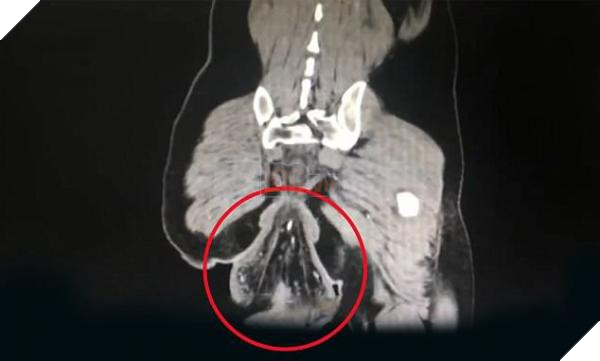

Hình ảnh chụp cắt lớp vi tính (CT) cho thấy phần ruột bị lòi ra dài khoảng 16 cm và có hình bầu dục. Có những vết bầm tím và nốt xuất huyết trên thành ruột.

Hình ảnh chụp CT của bệnh nhân. Ảnh: Kan Kan News